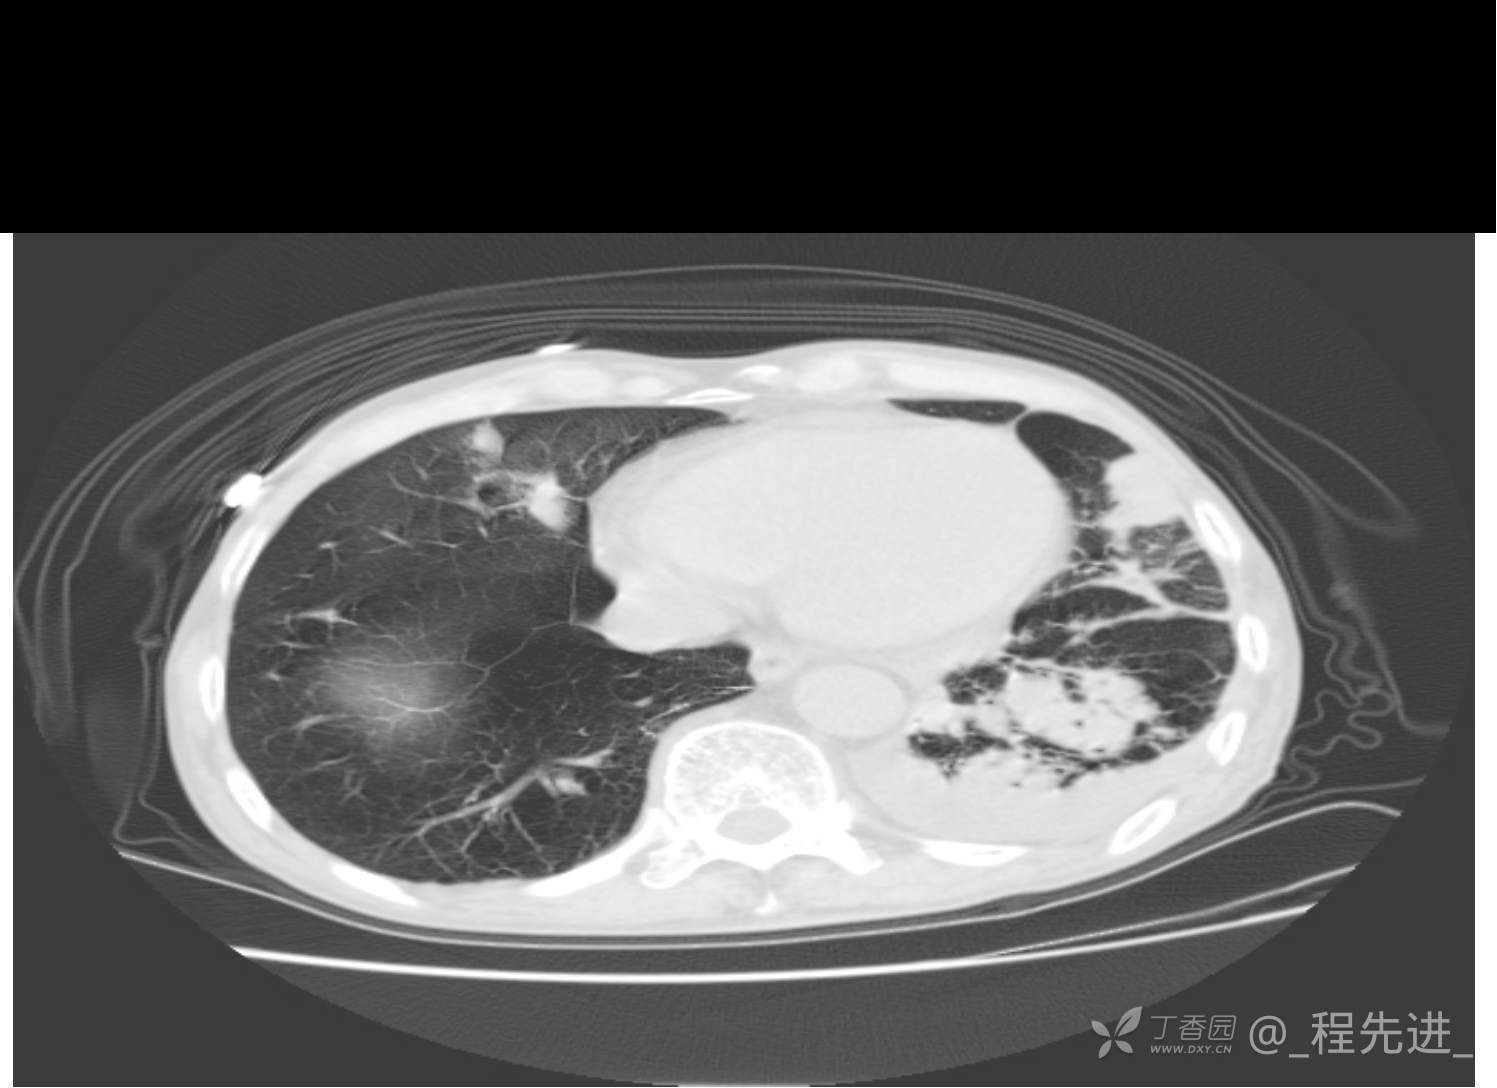

患者性别:男

患者年龄:81岁

简要病史:反复咳嗽、咳痰20余年,加重1周。两肺呼吸音低,可闻及散在干湿啰音。